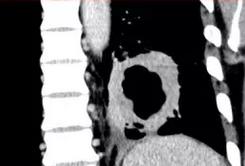

有一种例外:当肺癌合并感染的时候,会出现类似假象!

像上图这位老人,76岁,咳嗽、呼吸急促一个月,CT发现右肺巨大肿块,可见平行的支气管,增强扫描强化均匀,但经支气管镜证实,这是肺鳞癌合并了感染。

所以,发现此类病例,如果抗生素治疗后病灶基本吸收了,就没事了;如果病程反复迁延,时好时坏,进一步检查也是有必要的,比如支气管镜或者经皮肺穿刺等手段。